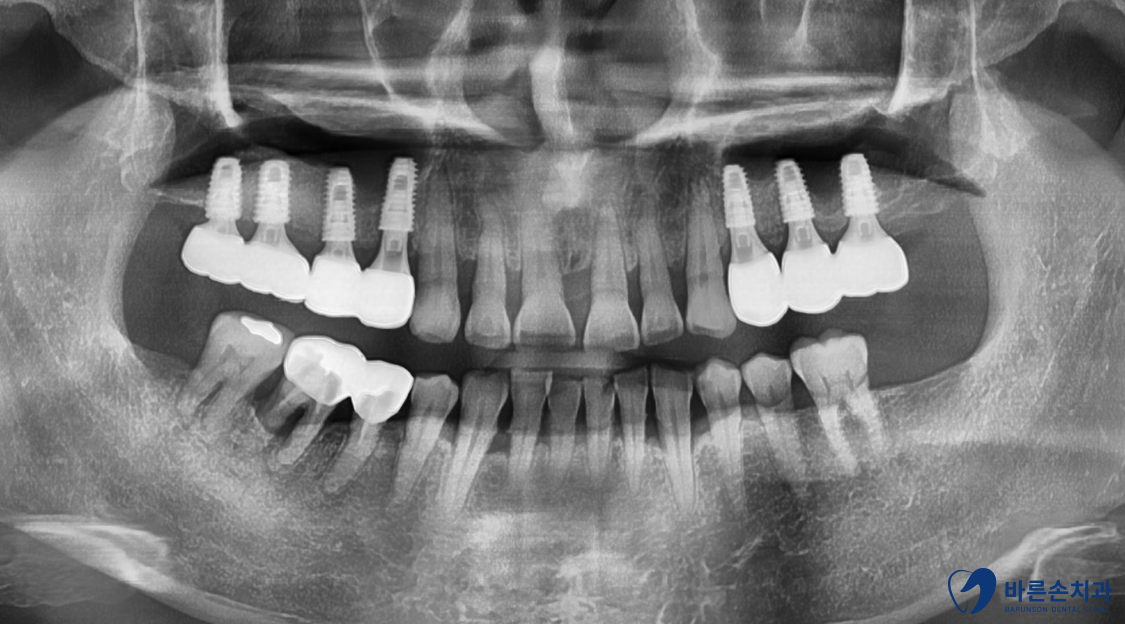

구내 엑스레이 사진을 보면 양쪽 위 어금니들이

빠진지가 오래되어 상악동 함기화가 되어

임플란트 식립할 뼈가 부족합니다.

X 표시가 되어있는 치아는 발치하고

왼쪽은 치아 3개, 오른쪽은 치아 4개를 만들기로 계획을 세웁니다.

왼쪽도 원래라면 4개의 어금니가 전부 있어야 하지만

아래 맞닿는 치아 하나가 어차피 없기 때문에

3개까지만 제작하기로 했습니다.

치료가 다 끝난 사진입니다!

임플란트도 뼈 안에 가지런히 잘 식립되어있습니다.